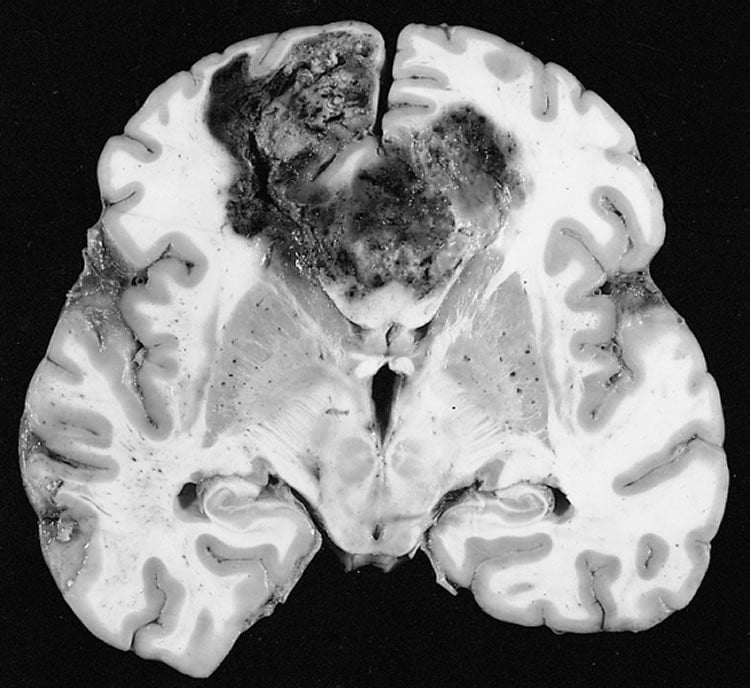

An experimental gene therapy essentially doubled the overall survival of patients with recurrent glioblastoma compared to the current standard of care, a researcher said Oct. 1 at the Cancer Therapy & Research Center (CTRC) at The University of Texas Health Science Center at San Antonio. Glioblastoma is an aggressive brain cancer that kills two-thirds of patients within five years. A patient’s outlook with recurrence of the disease is considered to be weeks or months.

Image Source: The image is credited to The Armed Forces Institute of Pathology and is in the public domain